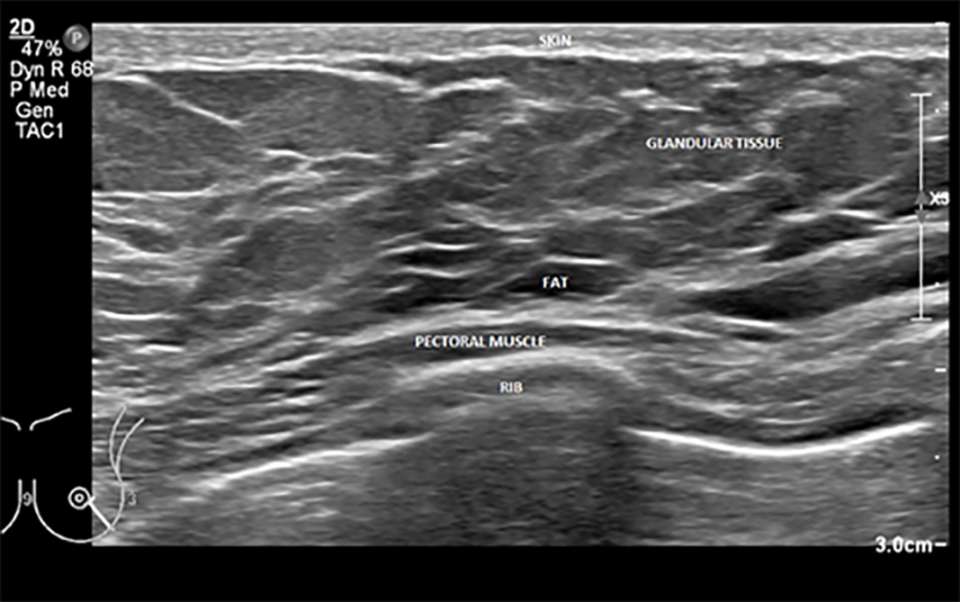

A labeled example of normal breast anatomy on ultrasound can be seen below. Of note, fat in the breast is hypoechoic, unlike ultrasound imaging of fat elsewhere in the body where is it primarily hyperechoic.

Basic of Breast Ultrasound Figure 4